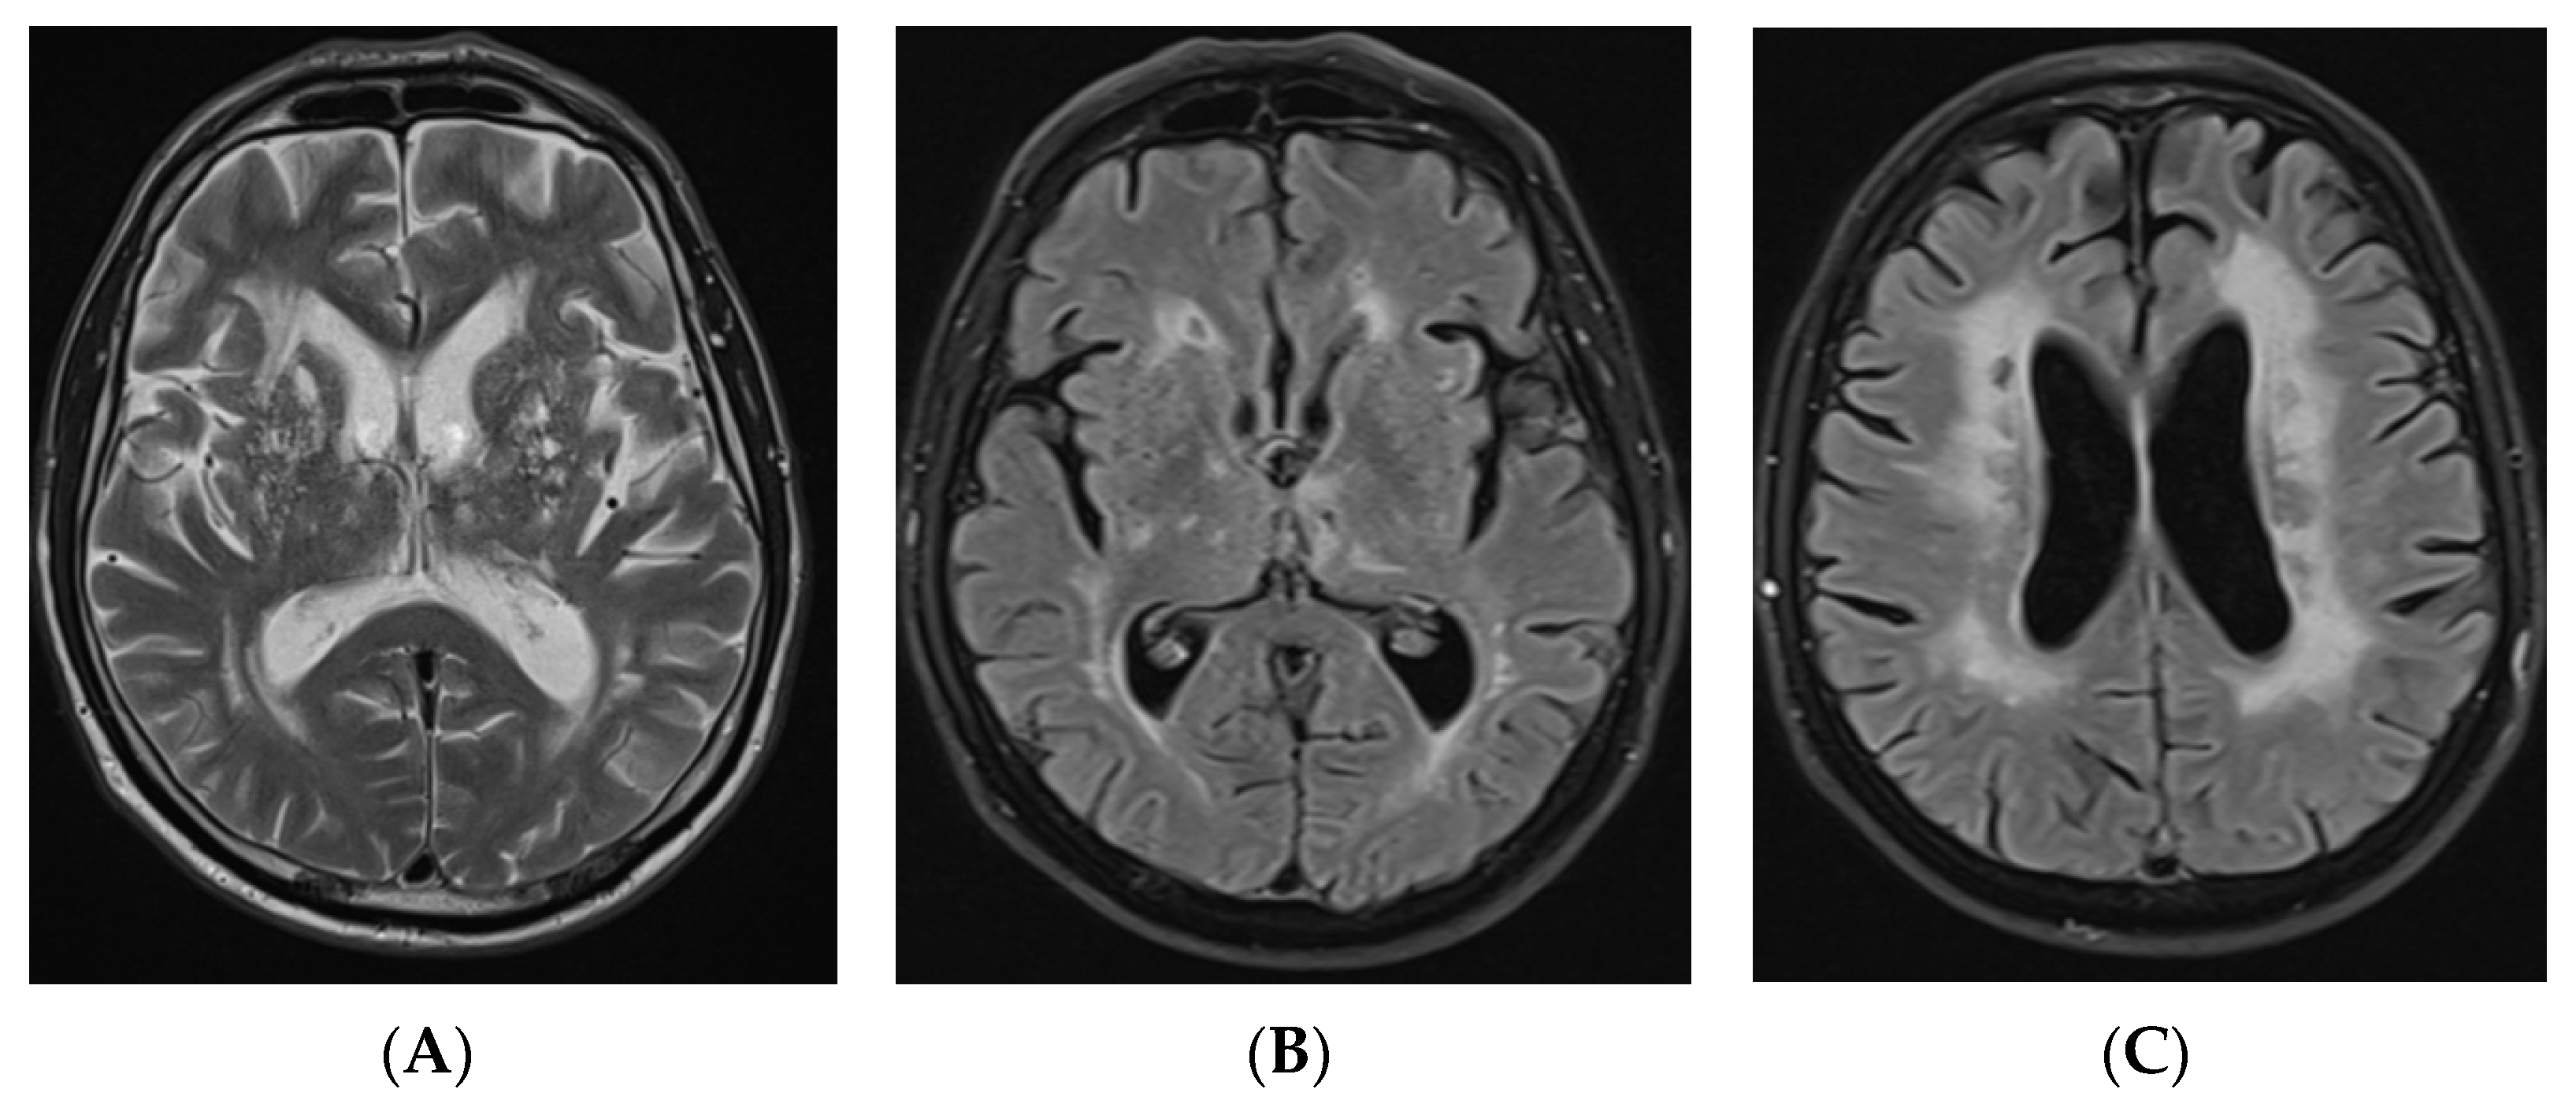

Since the patient developed early onset progressive dementia, had a stroke at a young age, several TIAs, and brain MRI was significant for extensive leukoencephalopathy, genetic testing by next generation sequencing for inherited cerebral small vessel disease was performed. On follow-up, the patient began manifesting positive psychiatric symptoms (hallucinations, delusions, anxiety) at the age of 60 that required several hospitalisations to the psychiatric ward. Cognitive functions further deteriorated from baseline MMSE score of 25 to 14 in 3 years, and the patient gradually became fully dependent in daily life. He also developed bladder and bowel incontinence and gait apraxia at the age of 62. In parallel, brain MRI showed evolution of findings: communicating hydrocephalus and leukoencephalopathy were progressing over time (HI was equal to 82, the width of the third ventricle was equal to 11 mm, Fazekas scale score 3), and new lacunar ischemic lesions and hemosiderin deposits appeared (Figure 2).

Figure 2. FLAIR axial images (A,B) and axial T2-weighted image (C) of brain MRI, performed after 3 years of initial brain MRI, demonstrating more subcortical and periventricular T2/T2 dark-fluid hyperintensities, Fazekas scale score 3, new lacunar lesions in right thalamus, progressive ventricular dilation (HI—82). FLAIR: fluid attenuated inversion recovery; MRI: magnetic resonance imaging; HI: Huckman index.